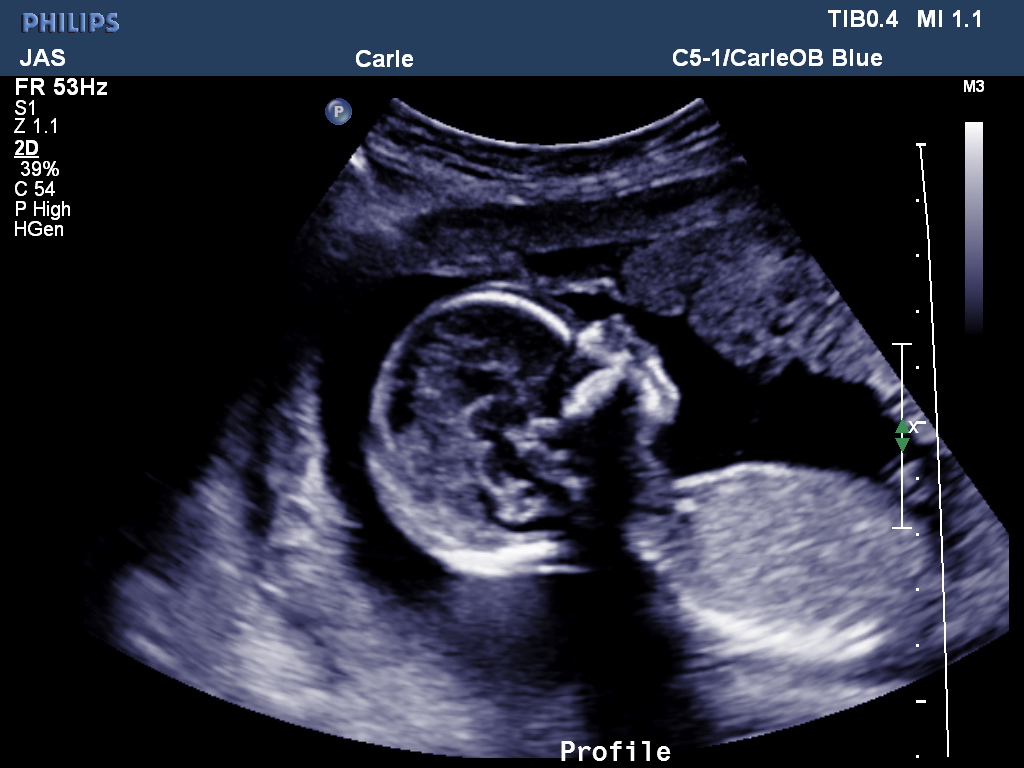

Here’s our baby girl: